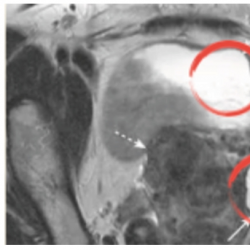

‘Glomerular hemorrhage’ was detected in T2 (right) instead of T1 (left).

‘Parotid pleomorphic adenoma’ detected in T1CE (right) instead of T1 (left).

The aim of this research is to generate MRI images with diverse contrasts solely from a single MRI image. For instance, given an input MRI image acquired with a T1 pulse sequence, the model can generate MRI images with T2, MRA, FLAIR contrasts, and more (as depicted in Fig.

1). This innovative approach has the potential to yield substantial benefits, including cost savings, time efficiency, and reduced patient discomfort, by eliminating the necessity for multiple MRI scans that require patients to remain motionless for prolonged periods. Moreover, taking the same anatomical structure in a different pulse sequence can assist diagnosticians in detecting underlying pathologies or injuries, such as brain tumours or oedema, as illustrated in Figs.

2,

3, and

4.

Fig. 4

‘Simple ovarian cyst’ detected in T2 (left) instead of T1 (right).